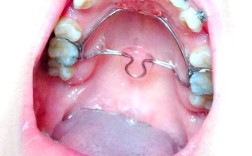

牙齿矫正是通过外力引导牙齿、颌骨及周围组织改建,最终实现咬合功能与面部美观协调的医疗过程,矫正器作为核心工具,根据作用机制可分为固定矫正器、活动矫正器及功能矫正器等,其中功能矫正器因其在调节颌骨发育、改善口腔肌功能方面的独特优势,在儿童及青...